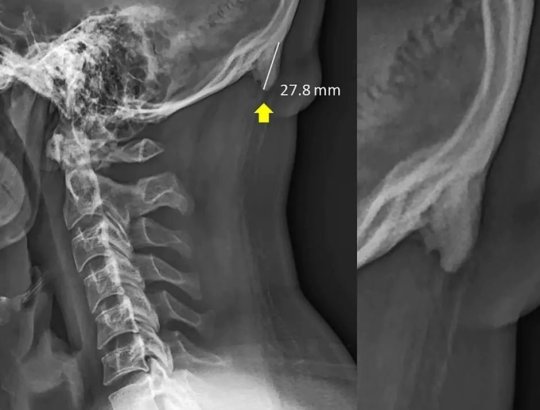

ツノの存在が明らかになったのは、両氏が2016年に若者を対象として行なったレントゲン検査時だ。18歳〜30歳の男女218人の内、実に41%に後頭部の骨の突起が確認されたという。

セイヤーズ氏は「1日の大半をスマホやゲームに費やすことで、首が下向きにうつむく時間が必然的に増加します。すると頭部の重みを支える比重が背骨から首や後頭部へと移動してしまうのです」と説明する。